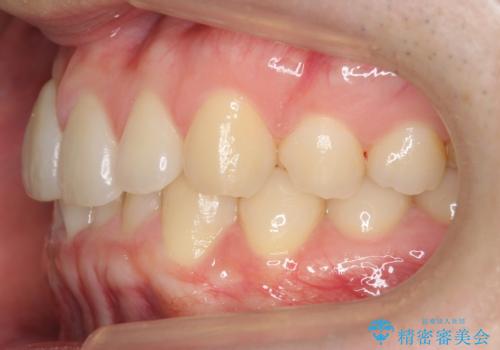

- 右上の前歯が内側に入っているのを気にして来院。

右上の奥歯を後ろに移動して、前に出すスペースを確保してから並べました。

奥歯を後ろに送るために、矯正用インプラントを使用しています。

前歯が内側に入っていると、笑った時にそこが黒くなり、歯が抜けたように見えます。

口を開けたとき、笑顔の印象が大きく変わり、大変喜んでいただけました。